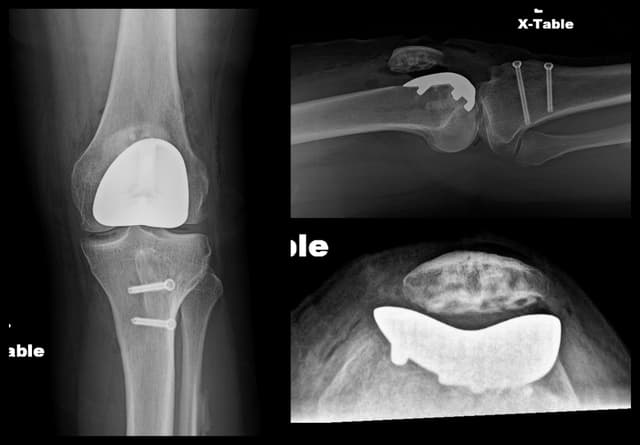

Pre-op

Post-op